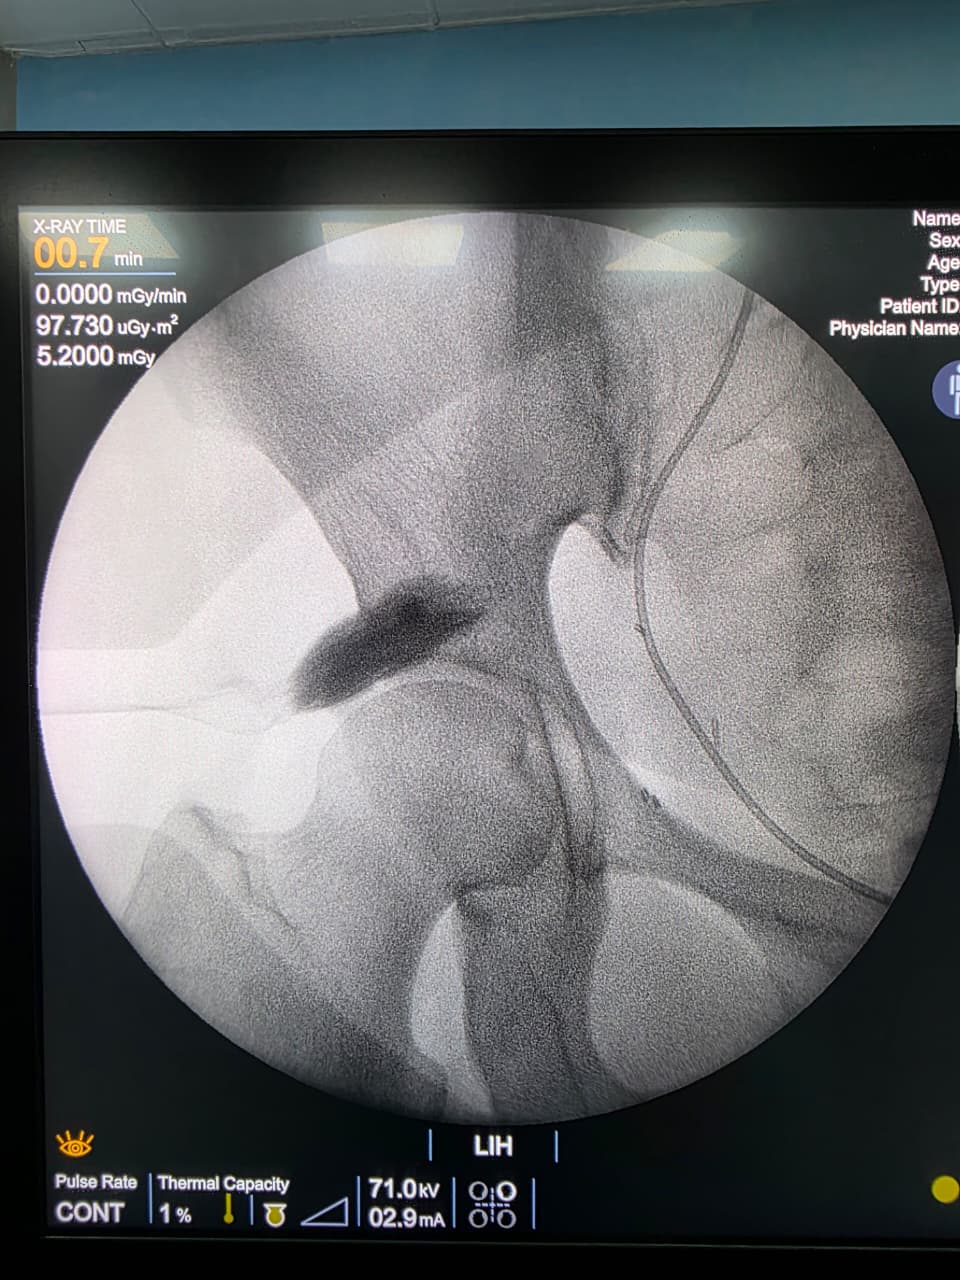

Procedures